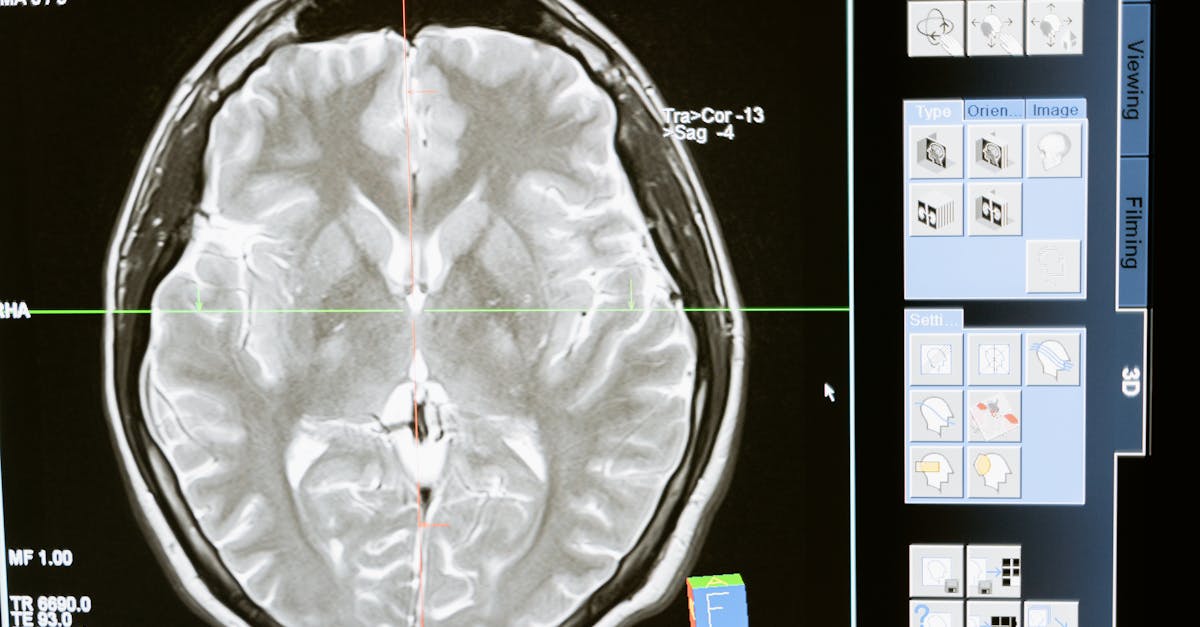

La réalisation d’examens d’imagerie est une étape clé. Une IRM standard peut souvent montrer des anomalies, mais pour un diagnostic plus précis, une IRM dynamique est recommandée. Cela permet d’observer le comportement de la colonne vertébrale en mouvement et d’identifier d’éventuels bombements discaux non visibles en position neutre.

Étape 2 : Imagerie médicale

Après l’évaluation clinique, il est essentiel de procéder à des examens d’imagerie médicale pour confirmer ou infirmer le diagnostic. L’IRM (Imagerie par Résonance Magnétique) est souvent privilégiée en raison de sa capacité à visualiser les tissus mous et les structures nerveuses. Ce type d’imagerie permet de déceler des anomalies comme les bombements discaux et la sténose du canal rachidien.

IRM dynamique

Lorsque les résultats de l’IRM standard sont ambigus, une IRM dynamique ou ciné-IRM peut être envisagée. Ce type d’imagerie génère des images du rachis en différentes positions, ce qui permet d’évaluer les changements du canal rachidien lors de l’extension ou de la flexion. Cela peut apporter des informations supplémentaires, notamment sur l’impact du bombement discal sur les racines nerveuses.

Une fois l’examen clinique effectué, le médecin peut recommander des examens d’imagerie pour compléter le diagnostic. Les IRM (imageries par résonance magnétique) sont couramment utilisées pour visualiser la colonne vertébrale et identifier des anomalies telles que la sténose et le bombement discal. Ces images permettent d’évaluer l’état des disques intervertébraux, la présence de hernies, et l’étroitesse du canal lombaire. Il est important de prendre en compte que parfois des IRM conventionnelles ne révèlent pas toujours des symptômes radiculaires. C’est ici que des techniques avancées comme la ciné-IRM peuvent jouer un rôle décisif.

Pour confirmer le diagnostic, des imageries médicales comme l’IRM ou la ciné-IRM sont souvent réalisées. Ces outils permettent de visualiser non seulement la morphologie du disque intervertébral, mais aussi son comportement sous contrainte lors des mouvements. Cela est particulièrement important pour déceler des conditions subtiles qui pourraient ne pas apparaître lors d’une simple IRM en position neutre.